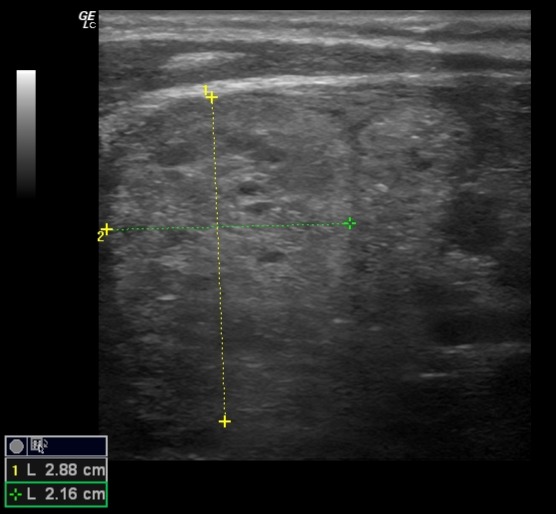

Ausencia de lóbulo izquierdo e istmo, en relación con cambios postquirúrgicos. Lóbulo tiroideo derecho aumentado, ocupado por conjunto de nódulos de aproximadamente 55 × 33 × 70 mm. Múltiples nódulos sólidos de ecogenicidad similar al parénquima; en Doppler se observa vascularización periférica. No se identifican adenopatías.

Se solicita ecografía preferente, cuyas conclusiones coinciden con las observadas: hallazgos compatibles con TI-RADS 3.